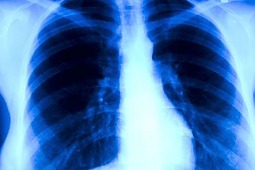

Zapalenie płuc wywołane P. jirovecii bardzo rzadkim powikłaniem u leczonych lekami biologicznymi

Postęp jaki dokonał się w leczeniu reumatoidalnego zapalenia stawów (rzs), wynikający z wprowadzenia leków biologicznych, związany jest również, ze zwiększonym ryzykiem infekcji oportunistycznych. Wśród najczęstszych wymieniane są zakażenia prątkiem gruźlicy, herpes zoster oraz listerią. Na zakażenie Pneumocystis jirovecii najbardziej narażone są osoby z niedoborem odporności, szczególnie zaburzeniami odpowiedzi T komórkowej. Również w przypadku chorych na rzs leczonych inhibitorami TNF alfa obserwowano przypadki infekcji tym patogenem.

Badacze brytyjscy na podstawie analizy danych zgromadzonych w rejestrze British Society for Rheumatology Biologics Register for RA (BSRBR-RA), opublikowali wyniki porównujące ryzyko zakażenia P. jirovecii wśród chorych na rzs leczonych syntetycznymi lekami modyfikującymi przebieg choroby (n=3677) oraz u leczonych inhibitorami TNF alfa (n=13905). W analizowanej populacji odnotowano 17 pewnych (potwierdzone badaniem mikrobiologicznym lub PCR) i 25 prawdopodobnych przypadków zapalenia płuc P. jirovecii (ci ostatni – to pacjenci leczeni z powodu zapalenia płuc odpowiadającego klinicznie P. jirovecii, u których nie potwierdzono mikrobiologicznie patogenu).

Ryzyko wystąpienia zapalenia płuc o etiologii Pneumocystis w grupie leczonej inhibitorami TNF alfa i syntetycznymi LMPCh, wynosiło odpowiednio 2,0/10 000 i 1,1/10 000 osobo-lat. Jak wskazują wyniki analizy, objawy infekcji ujawniają się we wczesnym okresie leczenia. Średni czas od rozpoczęcia leczenia inhibitorem TNF alfa, do wystąpienia objawów zapalenia płuc wynosił blisko sześć miesięcy. Może to wskazywać, że pneumonia P. jirovecii, w tej populacji pacjentów, jest następstwem reaktywacji latentnego zakażenia.